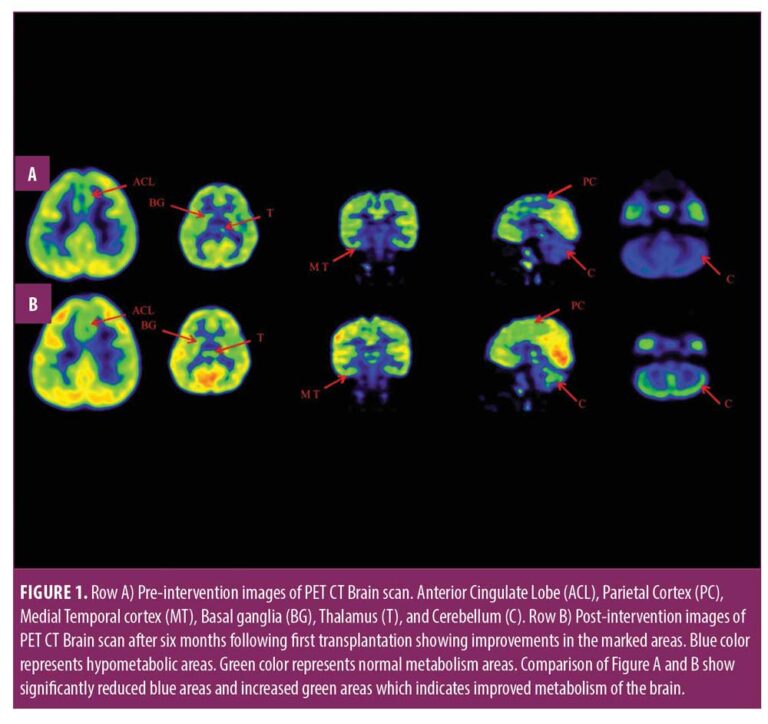

本报告中,我们治疗了一名患有痉挛性双瘫性脑瘫的儿童,在对康复反应有限后,采用了多种细胞疗法。临床改善的结果与客观量表相关,例如粗大运动功能测量 (GMFM)、粗大运动功能分类系统 (GMFCS) 以及功能独立测量 (FIM) 和 (PET CT) 脑成像研究。

在认知上,由于他定期上学,他的注意力持续时间和坐姿耐受力也得到了改善。GMFM分数从60.67提高到67。GMFCS等级由3级提升至2级;FIM评分从97分提高到99分。比较第一次细胞治疗之前和之后7个月期间进行的脑部PET CT扫描结果,发现前扣带回叶、顶叶皮层、内侧颞叶皮层、丘脑、基底神经节和小脑(表1)。

在此,我们通过客观量表(如FIM、GMFM和GMFCS)和正电子发射计算机断层扫描脑神经影像对比研究来监测细胞疗法后的疗效。在16个月的治疗过程中,GMFM评分从60.67分提高到81.88分,其中坐的领域从59分提高到60分,爬行和跪的领域从32分提高到40分,站的领域从6分提高到27分,走、跑和跳的领域从8分提高到32分。GMFCS 分级从第3级提高到第2级,因为孩子能够腾出双手坐在椅子上,能够在没有帮助的情况下在平整的地面上行走和奔跑,还能够扶着栏杆爬楼梯。FIM分数从91分提高到99分,这表明他的功能状况有所改善。

这项研究表明,多种干细胞疗法结合神经康复可有效改善脑瘫患者的粗大运动功能和功能独立性。自体BMMNC多次移植后进行强烈的神经康复可加快神经再生过程,这反过来又反映了患者残疾程度和生活质量的积极结果。PET CT扫描可以有效地用于监测干预后细胞水平发生的变化。因此,多细胞疗法是安全、可行的,并且可以有效地与脑瘫的神经康复相结合作为增强治疗。